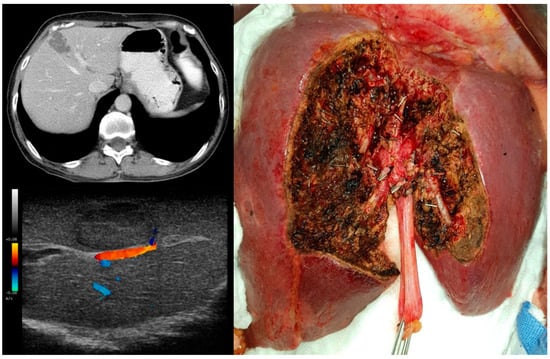

2. Materials and Methods

2.1. Design and Setting